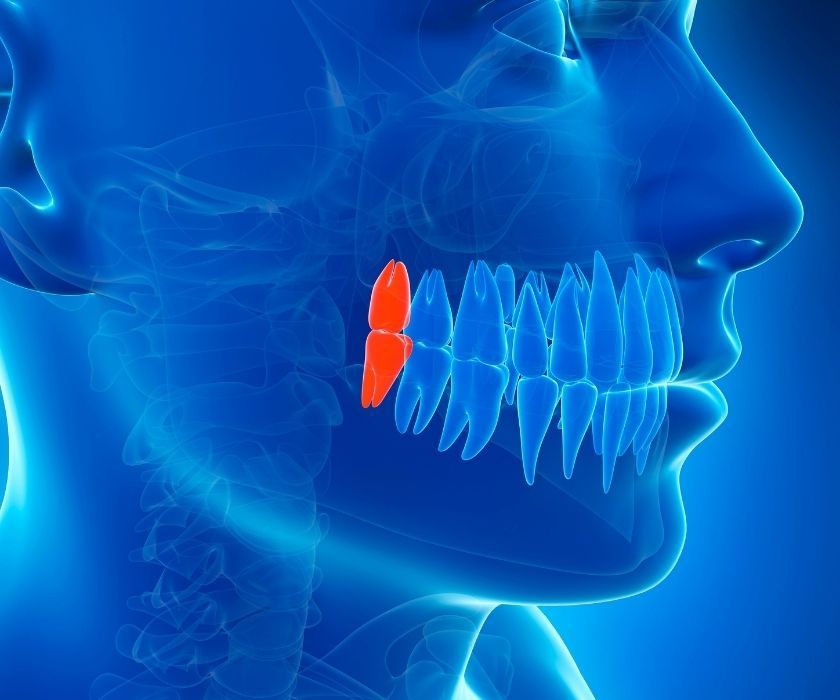

Nên đến nha khoa thăm khám để xác định có cần nhổ răng khôn mọc ngầm không

Nên đến nha khoa thăm khám để xác định có cần nhổ răng khôn mọc ngầm không